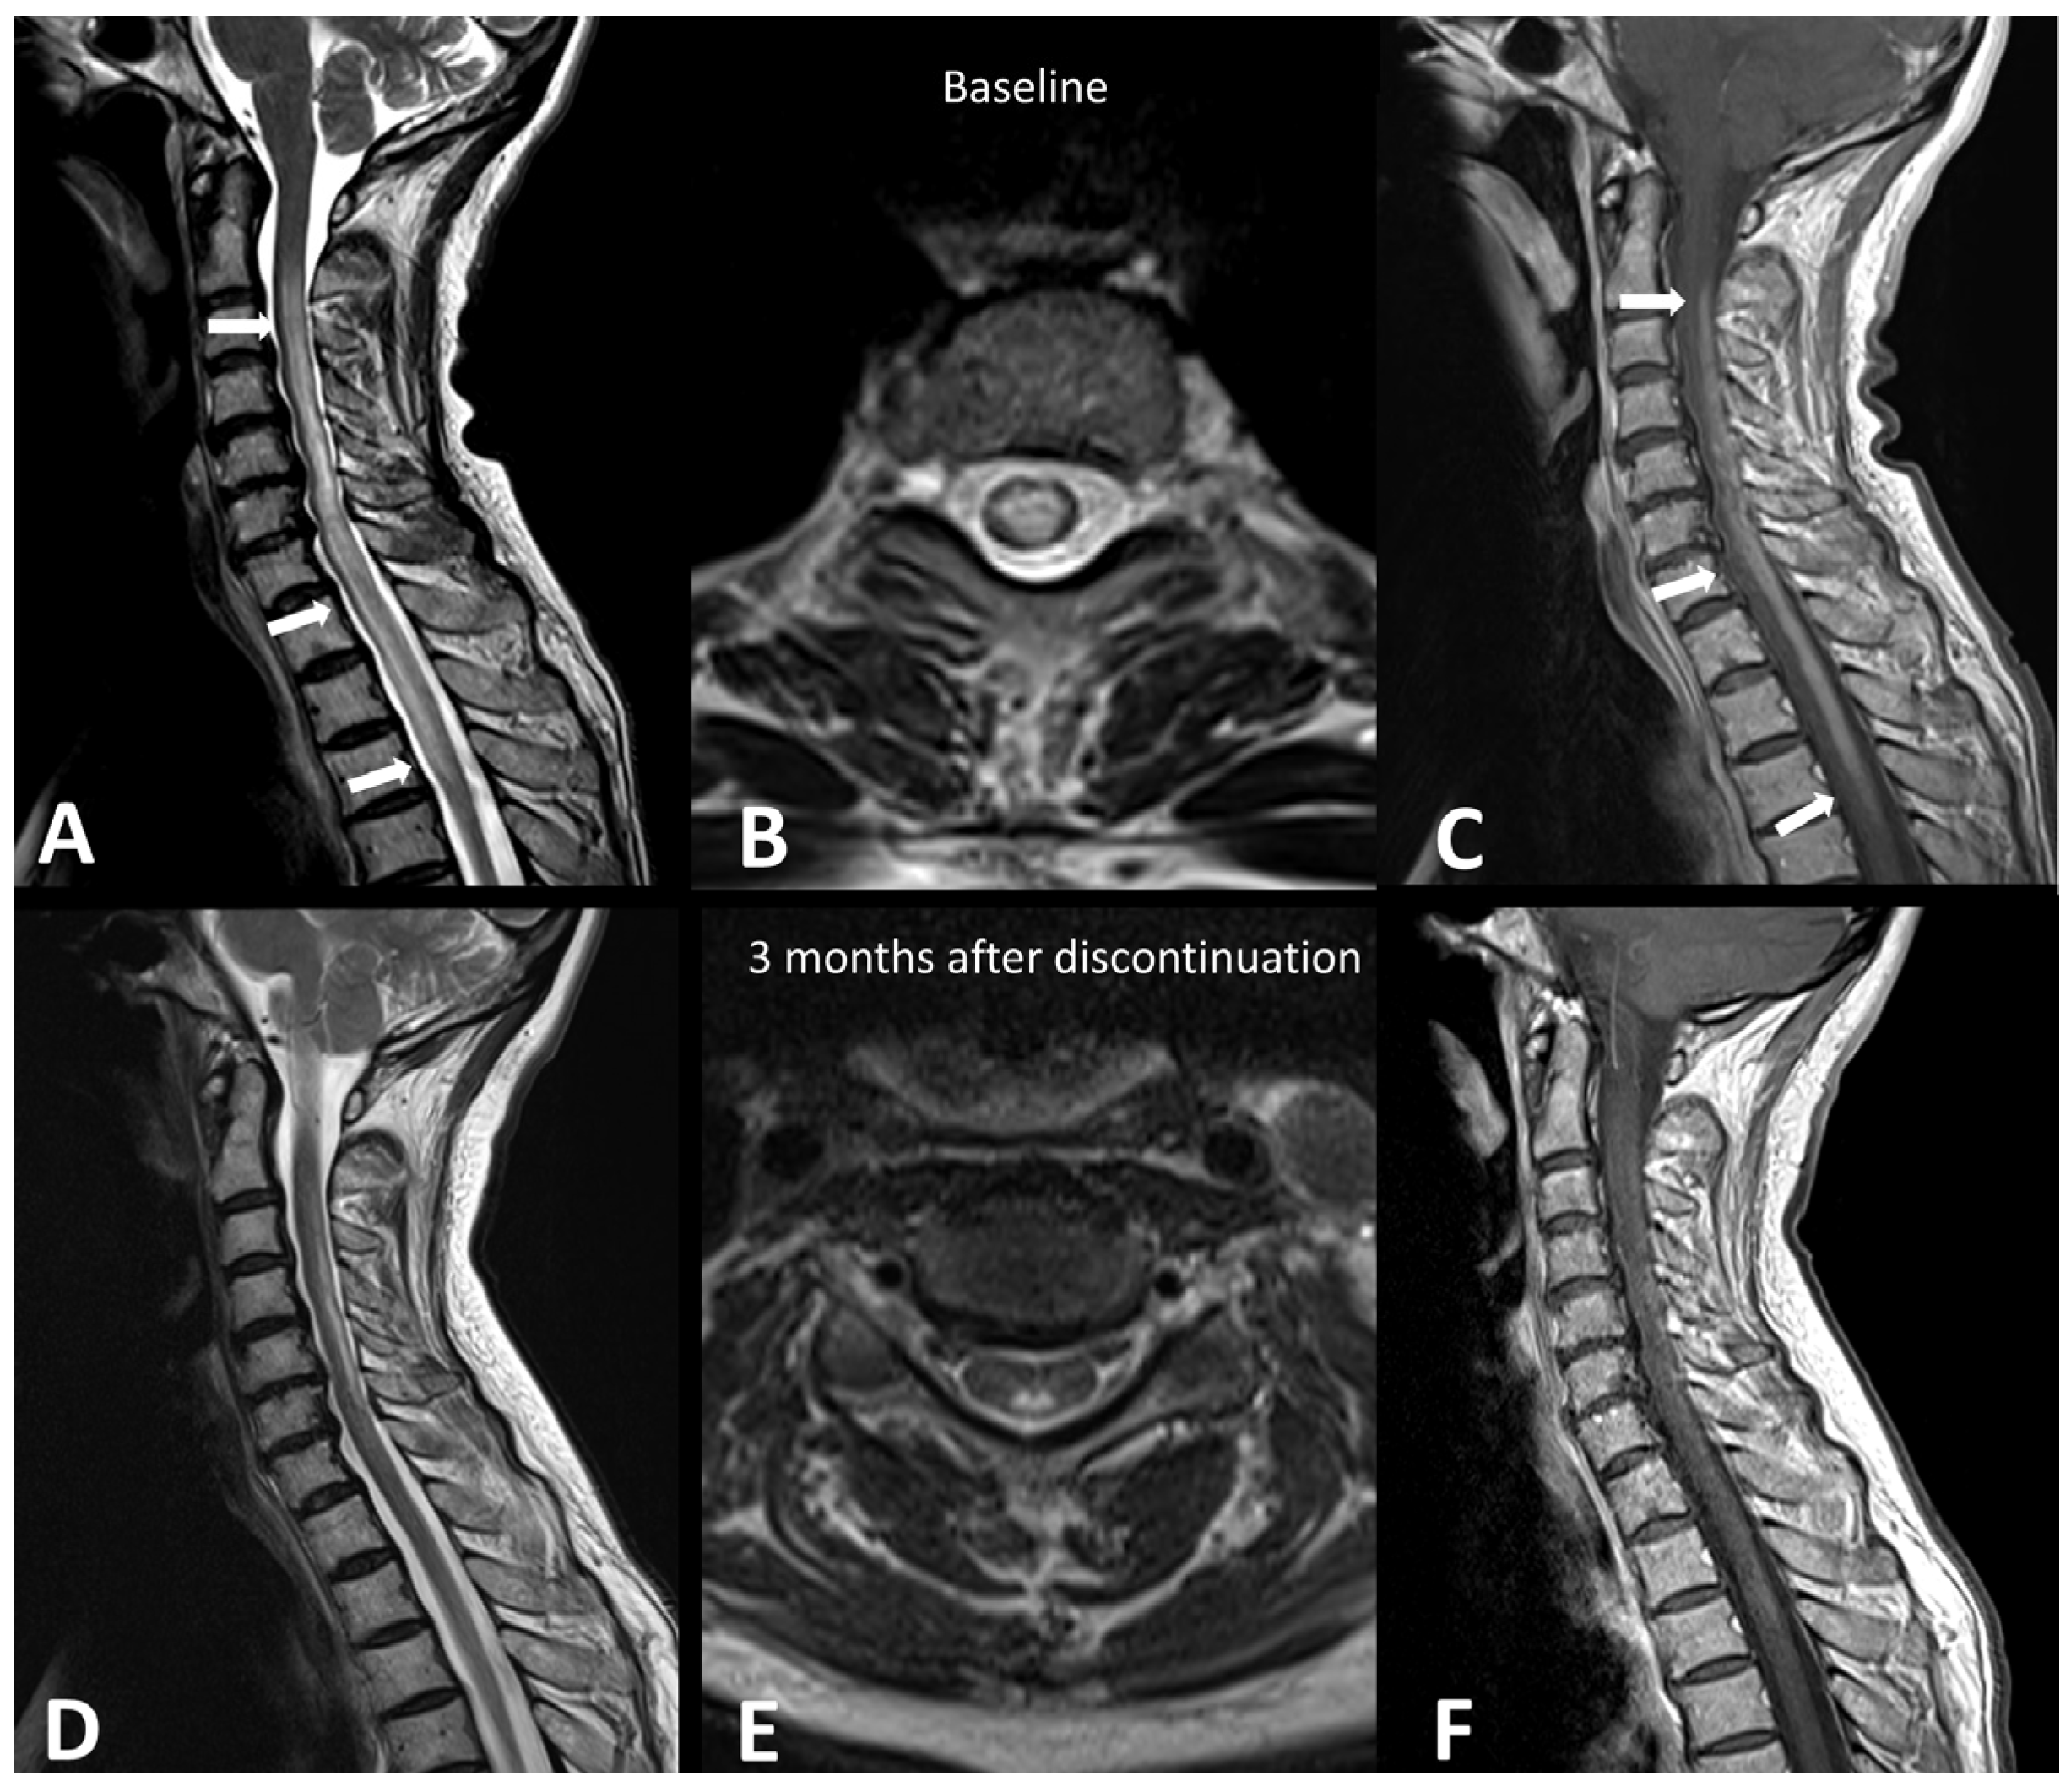

A recent systematic literature review of case reports demonstrated that demyelinating diseases, both typical and atypical, following ICIs, are very rare but still possible [21]. Clinical presentation depends on the anatomical site of the demyelinating process. The clinical workup may include MRI of the brain, spine, and optic nerves, LP, and autoantibody evaluation. In accordance with the McDonald criteria, MRI lesions are considered demyelinating based on the presence of T2 hyperintensity and/or contrast enhancement and location in cortical, juxtacortical, periventricular, or infratentorial regions intra-cranially or in the spinal cord. In the spinal cord, hyperT2 lesions are more commonly longitudinally extensive, spanning three or more levels, and they are associated with spinal cord edema and patchy enhancement (Figure 1) [22]. MRI of the orbits can show optic nerve enhancement, typically sparing the retrobulbar and proximal segments [21].

Figure 1.

Immuno-related extensive myelitis in a patient suffering from left arm melanoma. The patient had diffuse sensitive symptoms in the forearms a few weeks after the beginning of antiPD-1 treatment. Medullary MRI revealed a T2 hypersignal on the T2 sequence involving more than three vertebrae on the sagittal plane (arrows in (A)) and more than 50% of the medullary diameter on the transverse plane (B). An extensive medullary enhancement is also seen (arrows in (C)). The treatment was suspended, and the patient was treated with intravenous immunoglobulin and prednisone. Medullary MRI performed 3 months after ICI discontinuation showed partial regression of T2 hyperintensities (D,E) as well as almost complete regression of the medullary enhancement (F).